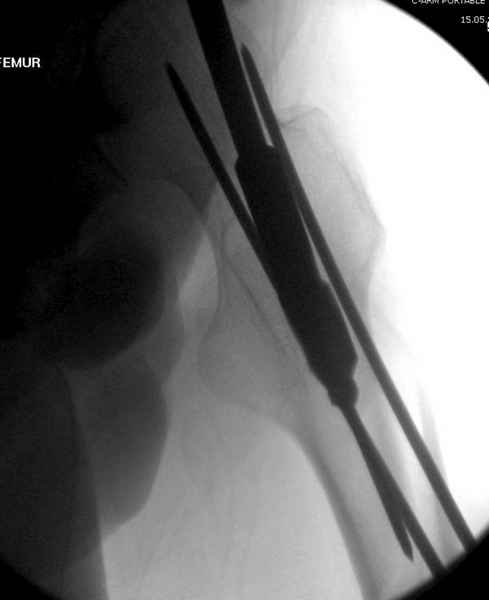

Учитывая, что случай ургентный, больной поступил вечером, не стали делать вытяжение и срочно провели операцию по фиксации перелома бедра антеградным штифтом Versa Nail от DePuy.

Для профилактики дальнейшего раскола в шейке предварительно во время проксимального рассверливания спереди и сзади провели временные спицы, которые в дальнейшем были заменены на шурупы (miss nail method)